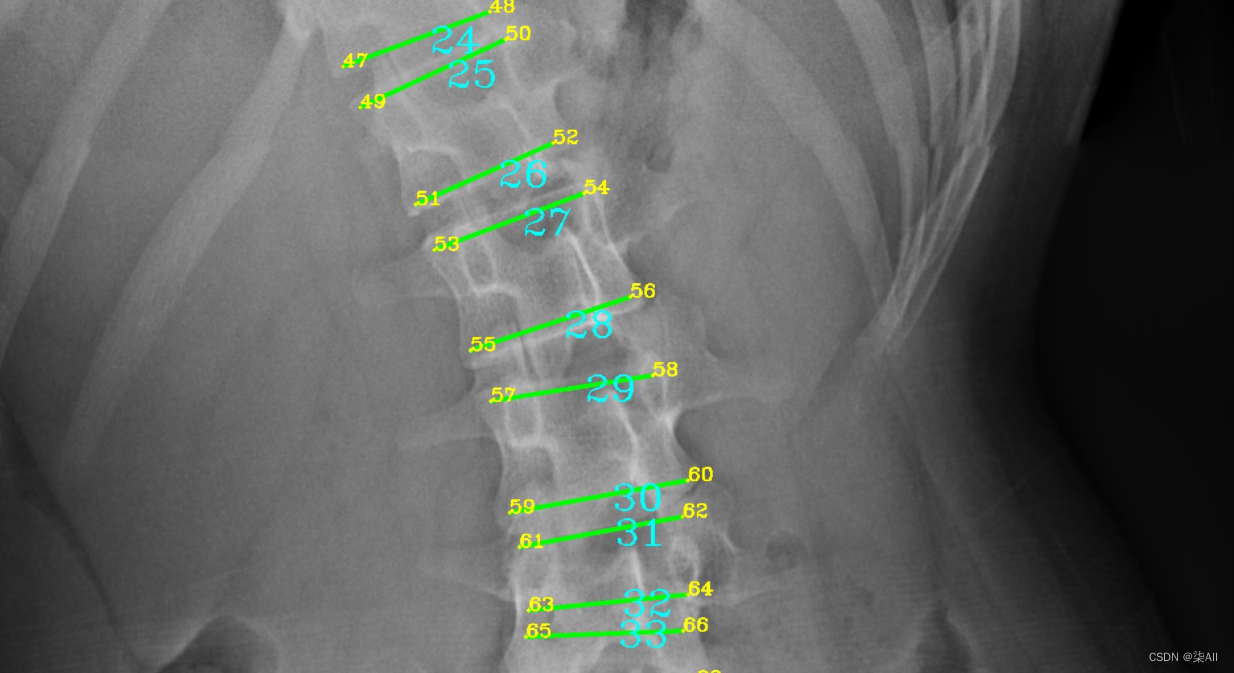

- (6)你看这种58这种点,咱们可以往外标一点,或者把60缩一些

###(5) 参考AASCE2019 GT图

(6)你看这种58这种点,咱们可以往外标一点,或者把60缩一些